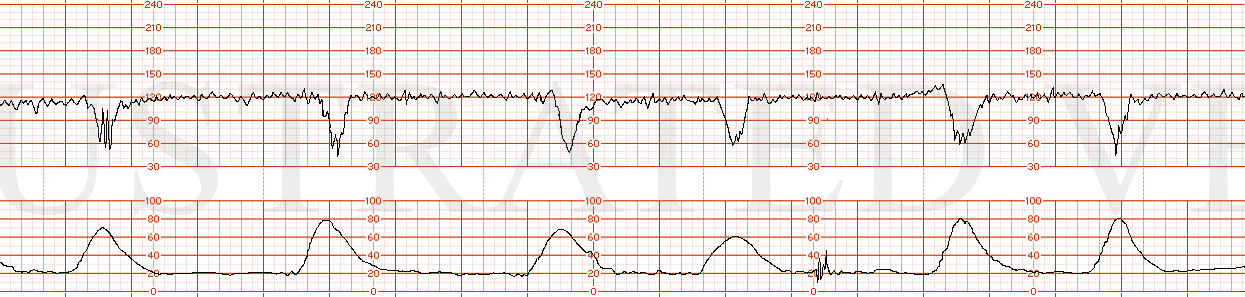

STRIP 72

1. 1st and 2nd panel:

Contractions: 7-8 60-70 second contractions in 20 min. (2nd too long by40 secs, 4th take off 10 secs, last 2 take off 20-30secs) See exception below re deceleration associated contractions – 3 run together concluding 30 sec or so before end of deceleration.

Baseline 140 bpm for first 5 minutes w 7-8 bpm variability

Decelerations deceleration x 5.5 minutes to initial nadir of 110 bpm x 45 seconds, followed by gradual return to 140 bpm. The deceleration parallels a triple contraction with total duration of 5 minutes – first contraction relative magnitude 1; second .75 and third .5 magnitude of first.

Variability1 average / moderate at 145 pm after deceleration

Accelerations no accelerations after deceleration

3rd panel:

Contractions2: 7-8 60-70 second contractions in 20 min. Contractions at more predictable intervals with no coupling or tripling of contractions (2nd, 4th 7th contraction too long

Baseline2 140 bpm for first 6 minutes

Decelerations2 One deceleration x 6 minutes to initial nadir of 115 bpm x 35 seconds, followed by gradual return to 150 bpm baseline

Variability2 average / moderate at 6-7 bpm at 145 bpm baseline rate after deceleration

Accelerations2 no accelerations after deceleration